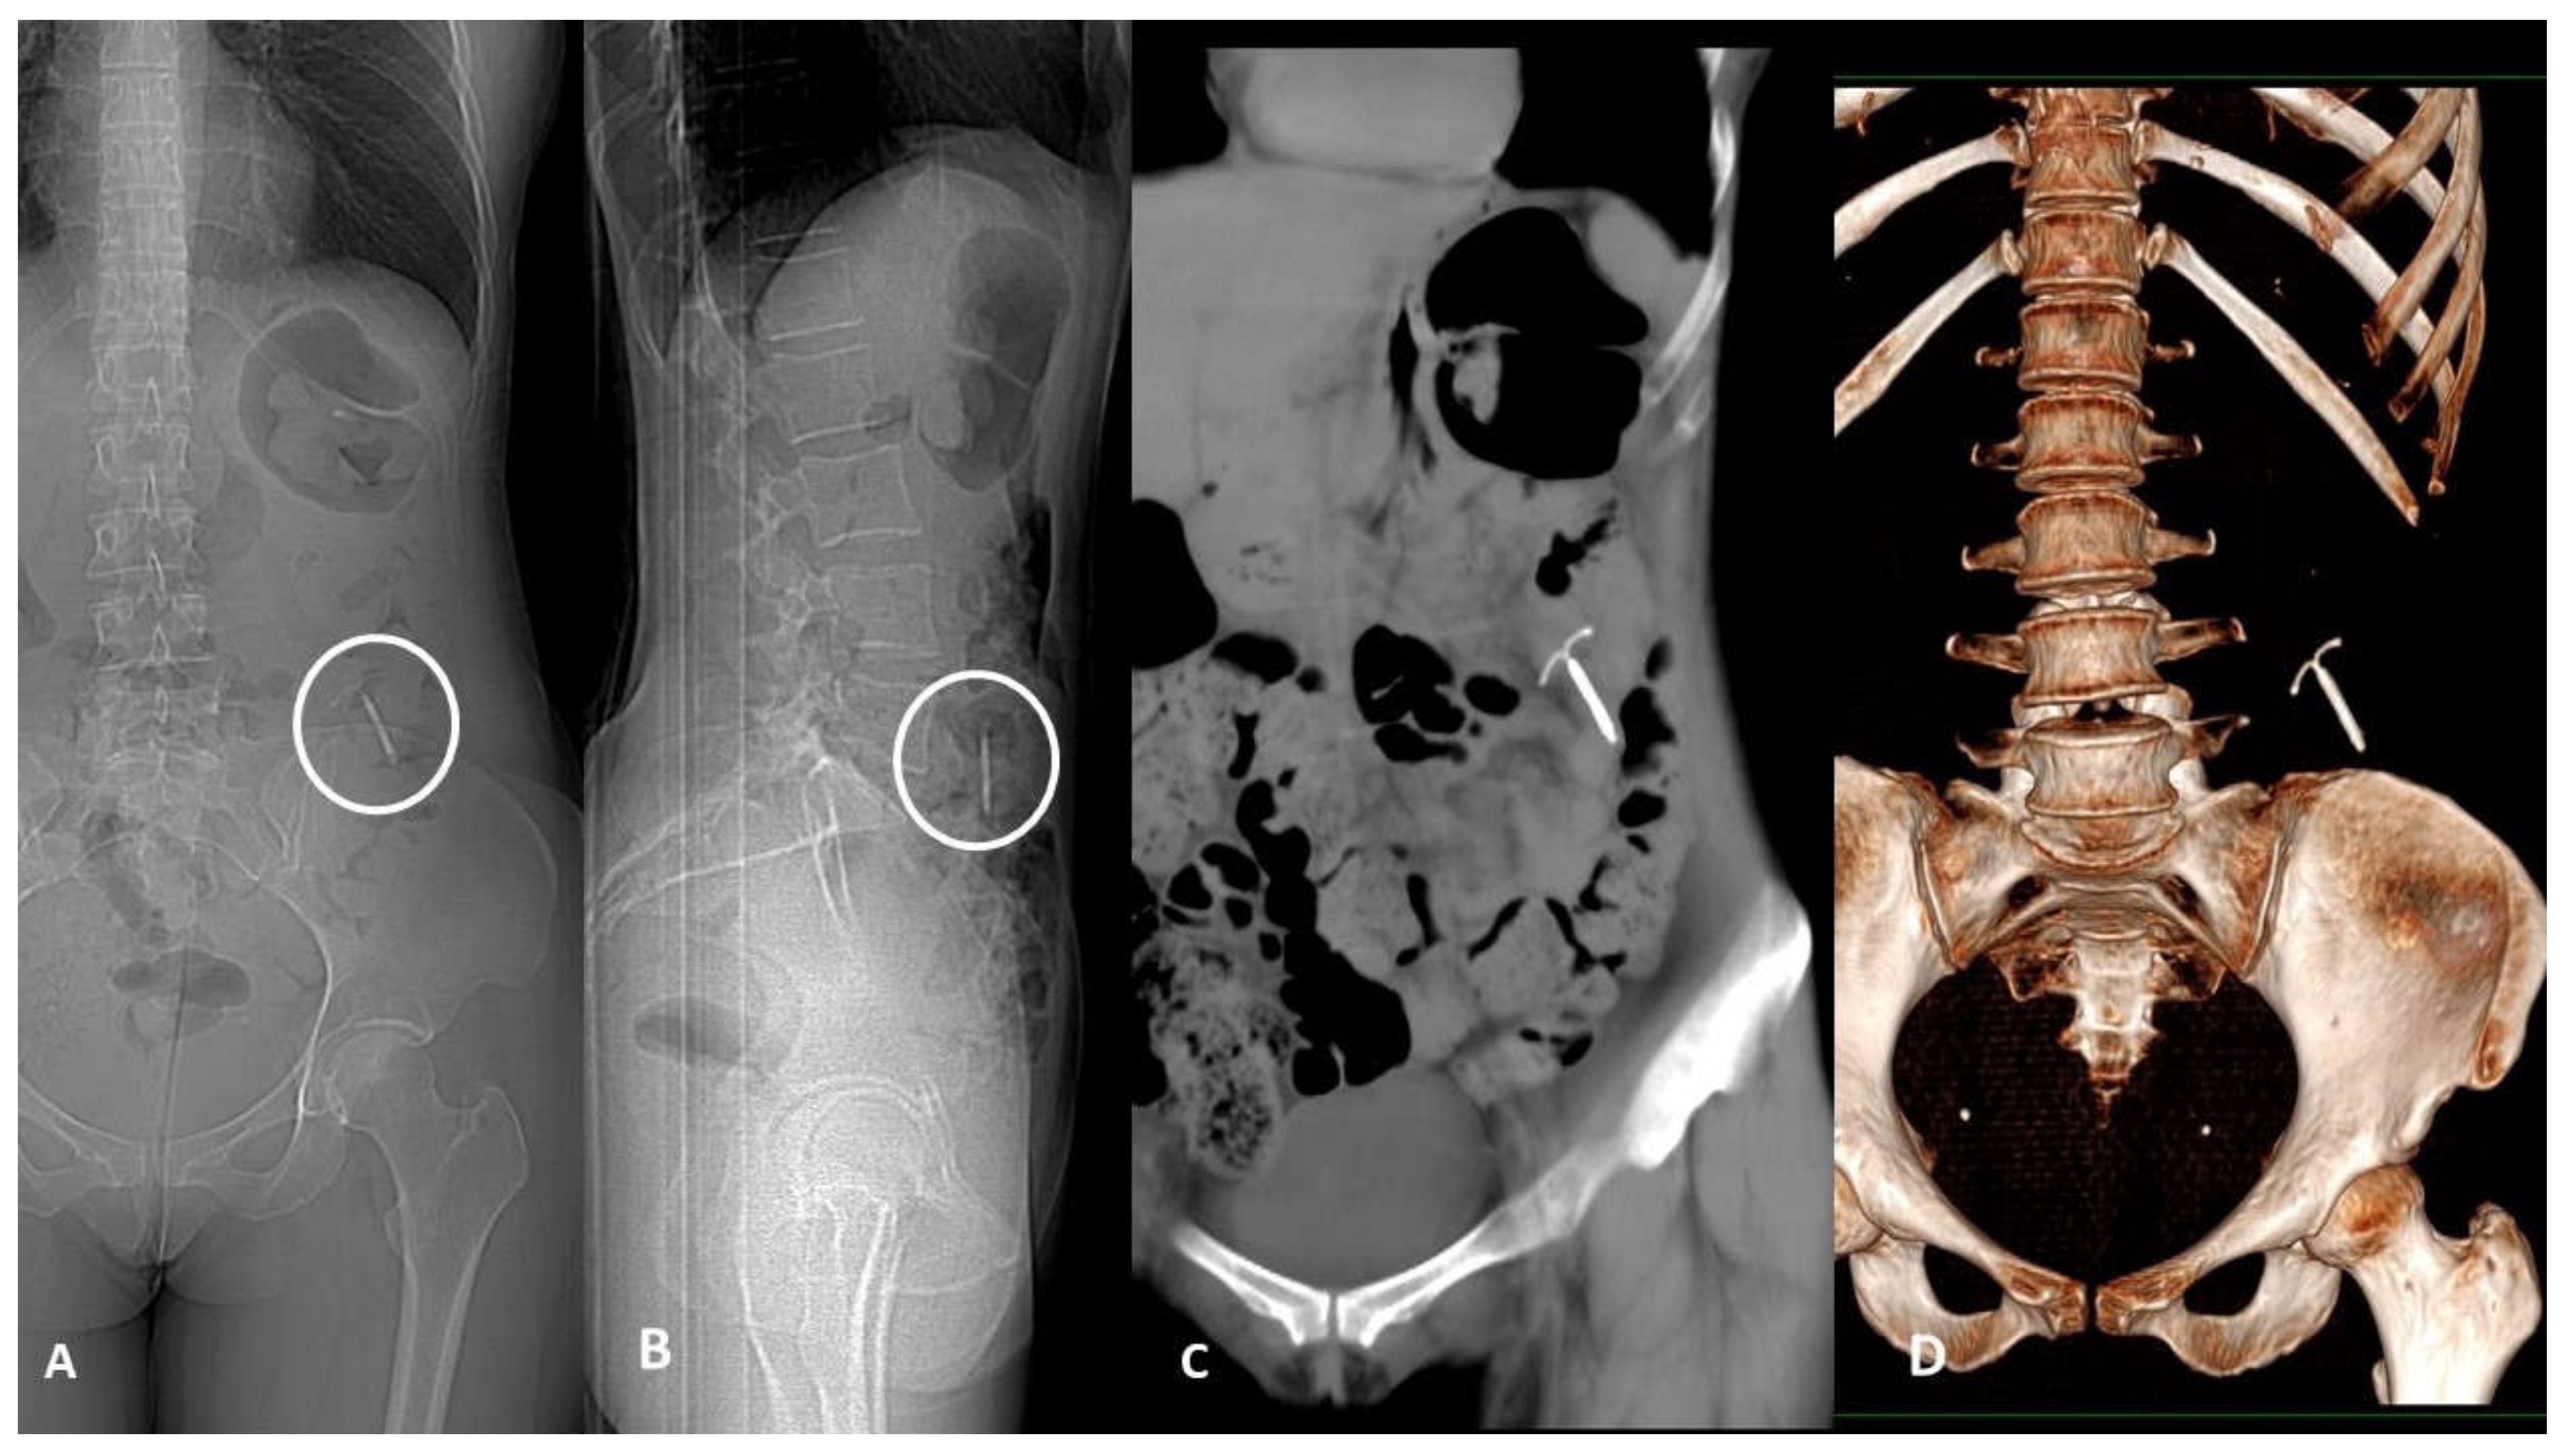

3. Device Integrity and Migration

- Contegiacomo, A.; Conti, M.; Trombatore, P.; Dezio, M.; Muciaccia, M.; Lozupone, E.; Natale, L.; Manfredi, R. Radiological features and management of retained needles. Br. J. Radiol. 2020, 93, 20200316. [Google Scholar] [CrossRef] [PubMed]